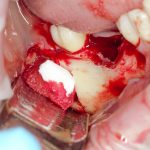

Далее, можем приступить к установке имплантатов. Разумеется. по хирургическому шаблону:

Последняя картинка даёт представление о том, какой объем костной ткани мы «нарастили».

Поскольку принимающее ложе и аутокостный блок конгруэнтны, мы можем отказаться от использования барьерной мембраны. Она не нужна.

Осталось только наложить швы:

и подождать 3-4 месяца до интеграции имплантов.